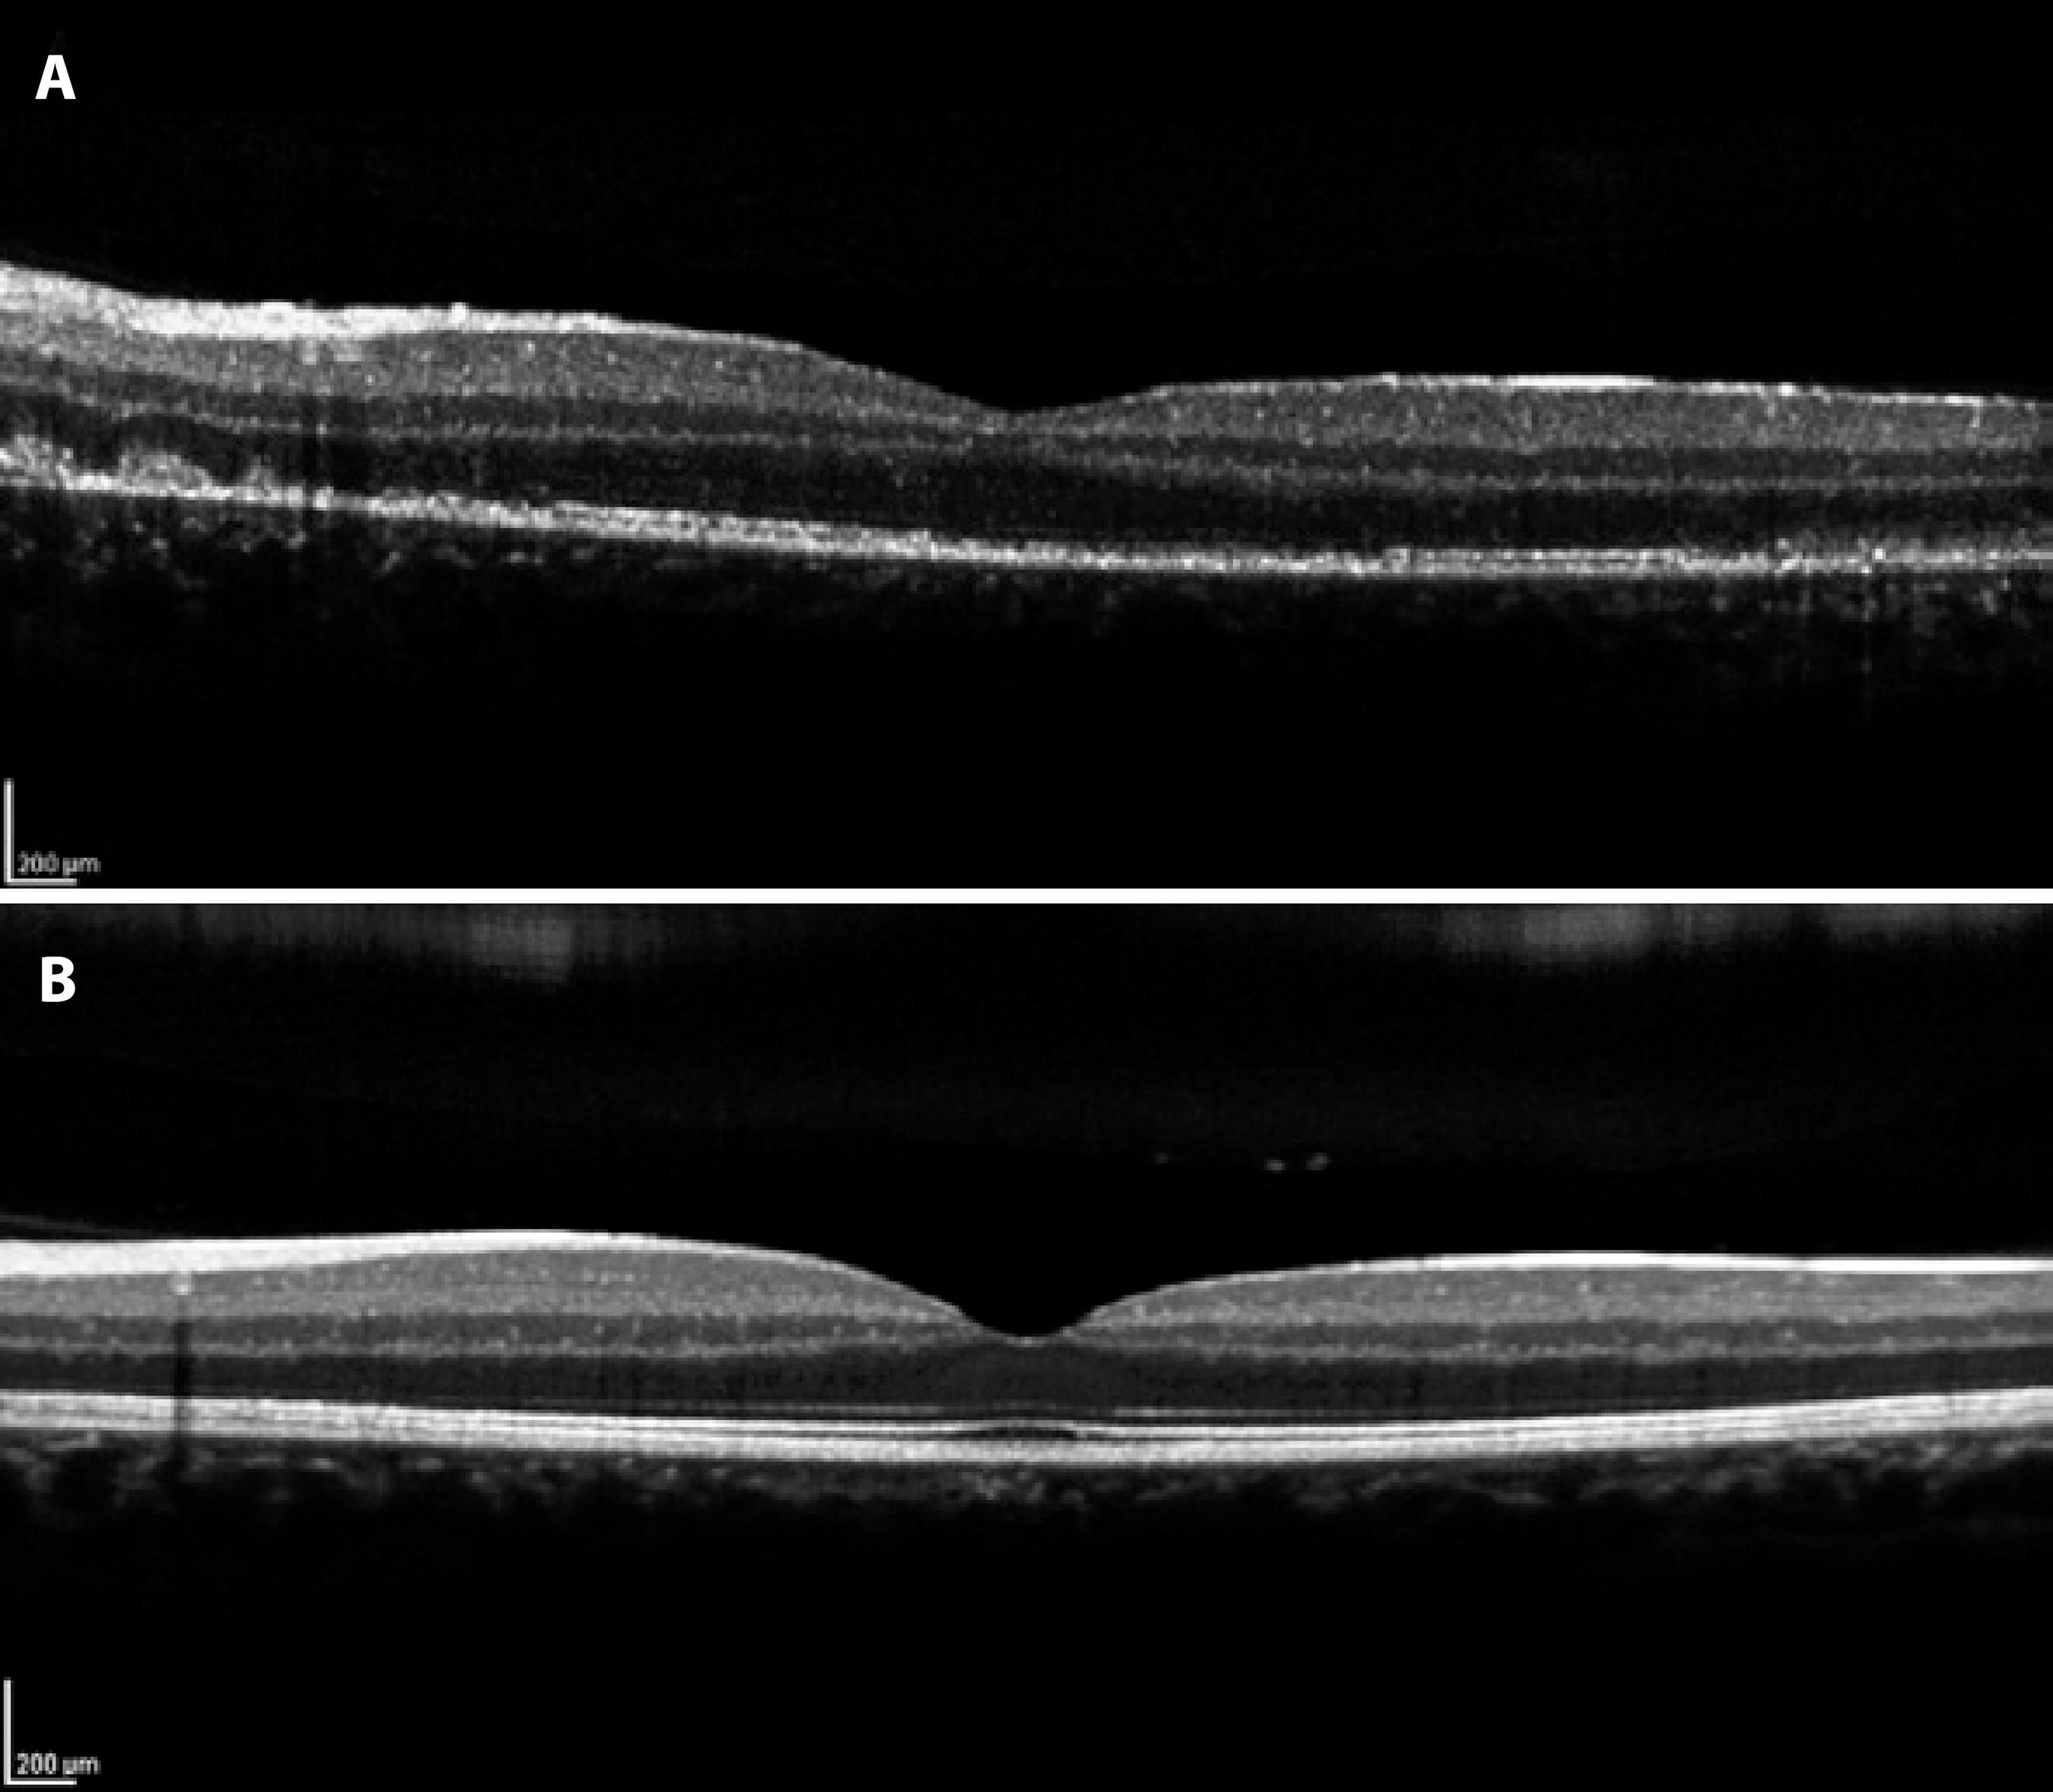

Automated perimetry showed a blind spot enlargement in the affected eye. FA had shown earlier hyperfluorescent lesions in the posterior pole and mid-periphery, with late staining of the white dots in a wreath-like pattern and late staining in the optic nerve (Figure 2). The corresponding ICGA demonstrated numerous hypofluorescent areas predominantly in the mid-periphery and around the optic disc. These hypofluorescent areas were mild and in an early angiographic phase, but became more clearly delineated in the late phase (Figure 2). SD-OCT showed mild attenuation of the external limiting membrane, a transient disruption of the macular photoreceptor IS-OS junction, increased RPE reflectivity and enhanced signal penetration into the underlying choroid (Figure 3). The patient was diagnosed with MEWDS and observation without treatment was suggested. The patient was lost at follow-up, but returned 24 weeks later after contacting the authors. He claimed that he had not attended the visits because he had visual recovery within one month. His BCVA was 20/20 OU. Fundus examination in the OD was normal, and the OS revealed mild foveal granularity and RPE hyperpigmentation surrounding the optic disc. Color and red-free fundus photography showed the retinal white dots disappeared. SD-OCT indicated the IS-OS disruption resolved with reestablishment of outer retina OCT anatomy (Figure 3).

Figure 3 A) Spectral Domain Optical Coherence Tomography (SD-OCT) demonstrating mild attenuation of the external limiting membrane, disruption of the macular photoreceptor inner segment-outer segment (IS-OS) junction, and increased RPE reflectivity. B) SD-OCT demonstrating resolution of IS-OS disruption with reestablishment of outer retina OCT anatomy.